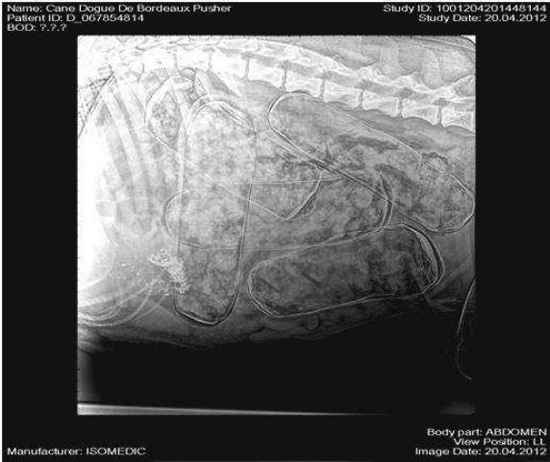

อย่างไรก็ดี นี่ไม่ใช่ครั้งแรกที่มีเจ้าหน้าที่พบการใช้สุนัขเพื่อขนยาเสพติดข้ามชายแดน เพราะไม่กี่ปีก่อนก็เคยพบสุนัขเลี้ยงแกะที่ถูกบังคับให้กลืนโคเคนลงท้องเพื่อข้ามฝั่งจากโคลอมเบียไปยังนิวยอร์ก แต่เจ้าหน้าที่ศุลกากรได้สังเกตว่าสุนัขตัวดังกล่าวมีอาการป่วยผิดปกติ จึงลองเอกซเรย์ดู แล้วก็ต้องตะลึงเมื่อได้พบว่าภายในท้องของสุนัขมีห่อโคเคนอัดแน่นอยู่ถึง 10 ห่อด้วยกัน